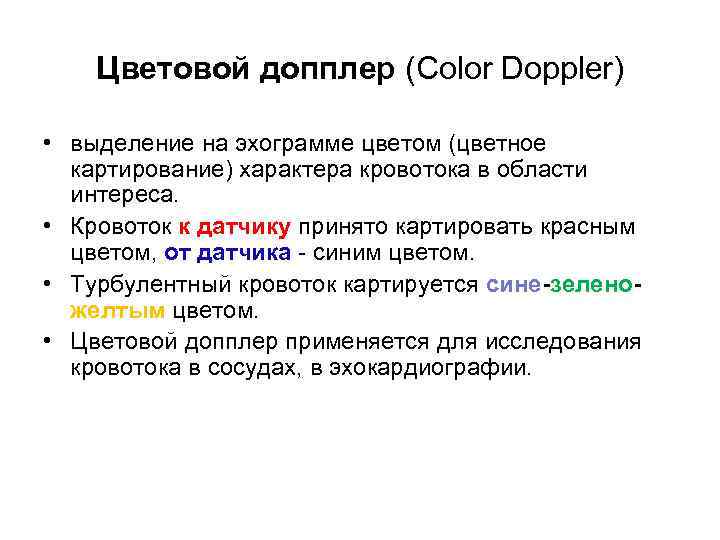

Цветовой допплер (Color Doppler)

Цветовой допплер (Color Doppler)

Цветовой допплер (Color Doppler) • выделение на эхограмме цветом (цветное картирование) характера кровотока в области интереса. • Кровоток к датчику принято картировать красным цветом, от датчика - синим цветом. • Турбулентный кровоток картируется сине-зеленожелтым цветом. • Цветовой допплер применяется для исследования кровотока в сосудах, в эхокардиографии.

Цветовой допплер (Color Doppler) • выделение на эхограмме цветом (цветное картирование) характера кровотока в области интереса. • Кровоток к датчику принято картировать красным цветом, от датчика - синим цветом. • Турбулентный кровоток картируется сине-зеленожелтым цветом. • Цветовой допплер применяется для исследования кровотока в сосудах, в эхокардиографии.

Цветовой допплер • Кровоток к датчику принято картировать красным цветом, • от датчика - синим цветом. • Турбулентный кровоток картируется сине-зелено-желтым цветом.

Цветовой допплер • Кровоток к датчику принято картировать красным цветом, • от датчика - синим цветом. • Турбулентный кровоток картируется сине-зелено-желтым цветом.